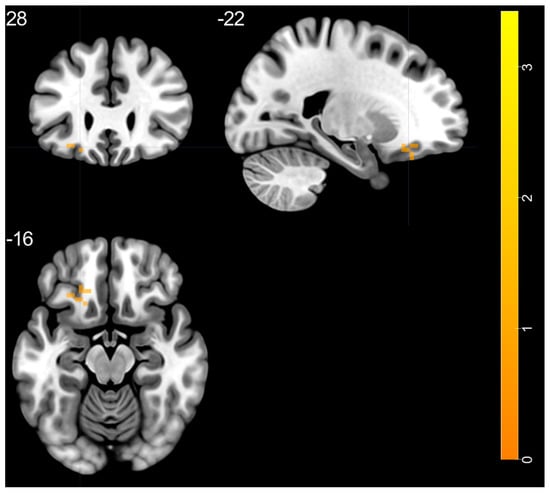

| Brain Regions | Peak T-Scores | MNI Coordinates | Cluster Size (Voxels) | ||

|---|---|---|---|---|---|

| x | y | z | |||

| BD > HC | |||||

| left STG—BA 20 | 4.525 | −48 | −24 | −6 | 38 |

| right putamen—BA 48 | 5.178 | 33 | −6 | 0 | 144 |

| right thalamus (ventral lateral nucleus) | 4.28 | 15 | −12 | 6 | 67 |

| left thalamus (ventral lateral nucleus) | 4.351 | −12 | −12 | 3 | 113 |

| left MOG—BA 19 | 5.075 | −24 | −60 | 33 | 58 |

| left SFG—BA 9 | 3.741 | −9 | 42 | 39 | 27 |